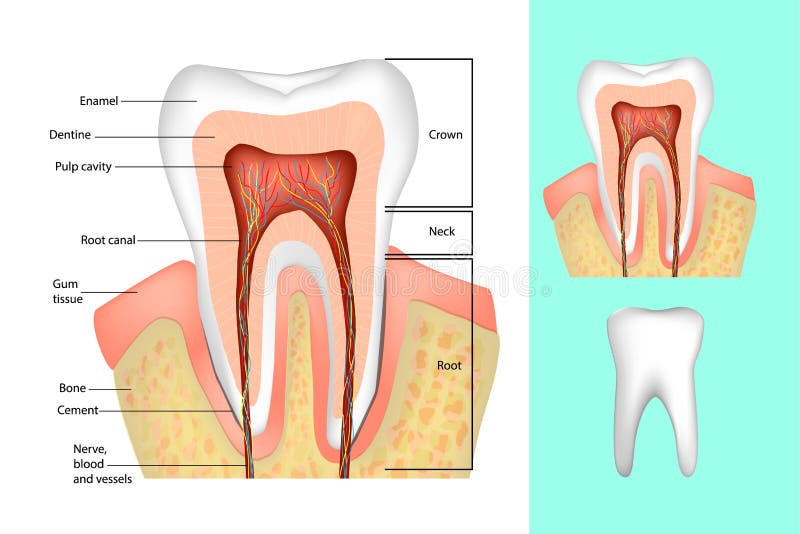

Tanden strukturerar Medicinskt diagram av strukturen av det inre tvärsnittet av tanden